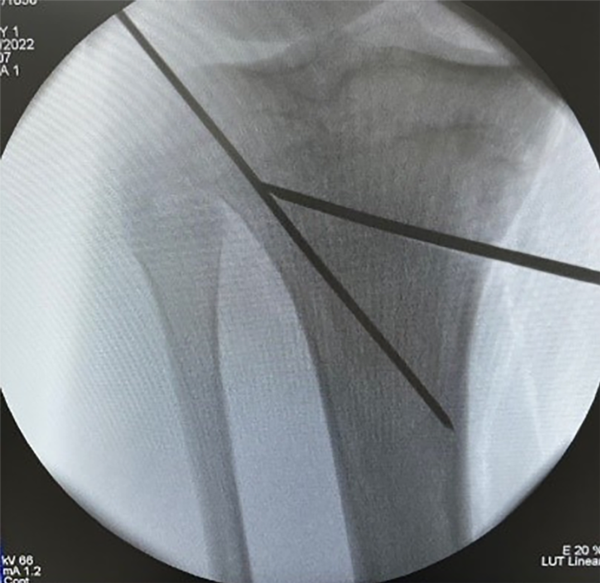

Matthew Olliver et al.34 realizaron un estudio retrospectivo de osteotomías y fracturas de la bisagra lateral, con uso de un pin protector de la bisagra, y sin este, posicionado desde anteromedial hasta lateral ubicado a 10 mm de la cortical lateral, concluyen que este pin actúa como un protector lateral, teniendo un papel que absorbe la fuerza al momento de abrir la osteotomía y también como un punto de tope de la sierra al momento de realizar el corte. Determinan, así, que reduce el número de fracturas intraoperatorias de la bisagra lateral y hasta las primeras seis semanas, tiene una disminución en el tiempo de consolidación y retorno al trabajo y al deporte11,34 (fig. 17).

Figura 17: Posicionamiento de los pines: se observa la aplicación intraoperatoria de la posición de los pines de la osteotomía y el pin de protección, en este caso se colocó anterógrado desde el ángulo posterolateral dirigido hacia la cortical medial a 10 mm de la cortical lateral.